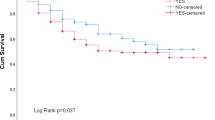

The ICC values for each model are shown in Fig. 1 demonstrating that each training model had an ICC > 0.9 indicating excellent agreement of all training models, and the ICC of the final test model was 0.954 also indicating excellent agreement. Figure 1 also displays the distribution of measured L3-CSA values with the predicted values for CSA using C3 measures demonstrating a high level of correlation with measured L3-CSA when validated on the test sample (r = 0.917, p < 0.001). Strong correlation was also found when comparing predicted and measured SMI values (r = 0.883, p < 0.001). Four patients had missing height and, therefore, were not included in the sarcopenia analysis. At L3 in the test sample, 20% of patients were classified as sarcopenic, 28% using the prediction model.

Testing of the prediction model demonstrated a sensitivity of 80.0% and specificity of 85.0%, with moderate agreement on sarcopenia diagnosis (k = 0.565, p = 0.004). Bland–Altman plots demonstrated good agreement with mean difference (bias) in CSA measures = 0.72 cm2 (SD 13.45, 95%CI − 4.71 to 6.15 cm2), limits of agreement (LoA) (− 25.65 to 27.09 cm2). Good agreement was also found on SMI with a low level of proportional bias, mean difference (bias) = 0.22% (SD 8.65, 95% CI − 3.35 to 3.79%), LoA (− 16.74 to 17.17%), well under the set a priori of 5% in the test population (Fig. 2).